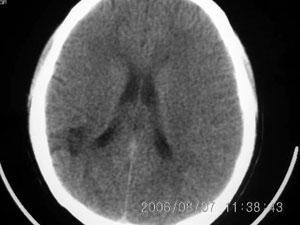

标题: CT4285:头部病变,女 21岁

女 21岁 发作性面色发白一年,每次发作仅数秒钟

局限性脑软化灶、脑萎缩,考虑动静脉畸形。

局部软化灶,脑沟增宽加深,考虑为脑血管畸形可能,建议增强或mri检查.

左颞顶叶不规则低迷度影边界尚清楚,岁数年轻,应考虑脑血管畸形。建议强化或核磁,进一步检查。

首先考虑avm,但脑囊虫病有没有可能?